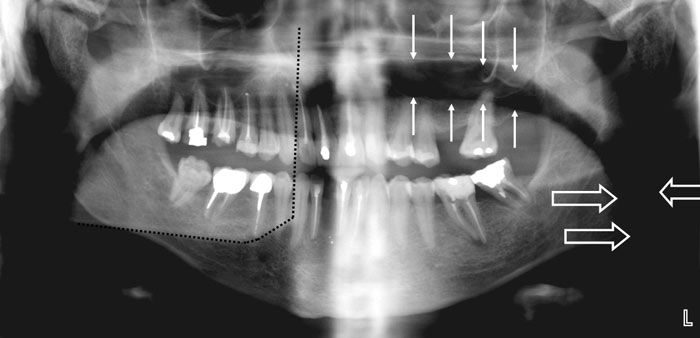

«Spøgelsesskygger» («ghost shadows») – opstår, når tætte (radiopake) objekter, der befinder sig uden for eller i yderkanten af skarphedszonen, afbildes andre steder på panoramabilledet end der, hvor de reelt er placeret. Typiske «spøgelsesskygger» er halshvirvelsøjlen, som afbildes i midten af panoramabilledet (Fig. 3A), modsatte sides underkæbevinkel, som afbildes i modsatte sideparti af panoramabilledet (Fig. 4) samt øreringe, som kaster «skygger» på modsatte side af billedet end der, hvor de reelt er placeret (Fig. 5).

Fig. 4. Panoramabillede med tydelig aftegning af luft i pharynx (blokpile) og mellem tungeryg og hårde gane (enkelte pile). Den stiplede linie markerer «spøgelsesskygge» fra venstre underkæbevinkel.